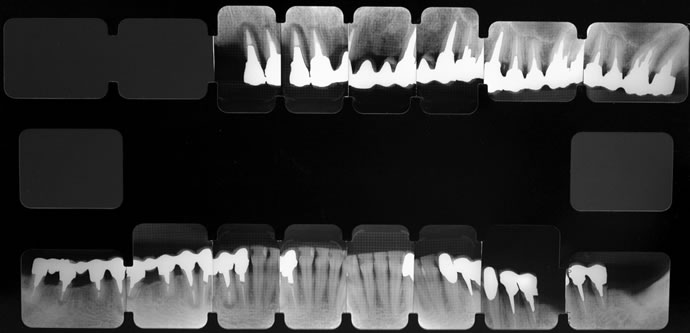

全体のレントゲン写真です。

上あごの前歯の歯の周囲に黒い影が見られます。このような場合、歯が割れて周りの骨が溶けていることが多いです。左下の歯は被せの下で虫歯が進行している状態です。